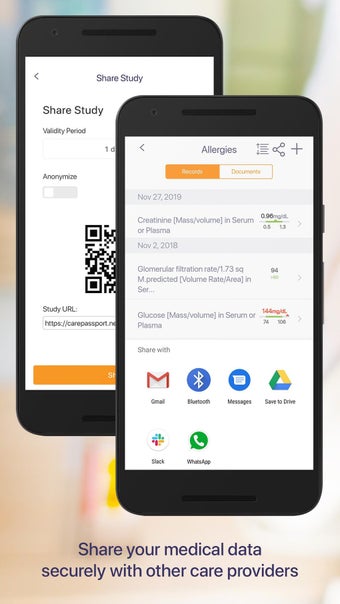

Carepassport là một ứng dụng Android cung cấp cho bệnh nhân một giải pháp toàn diện để quản lý dữ liệu y tế của họ. Ứng dụng cho phép bệnh nhân truy cập và lưu trữ an toàn dữ liệu y tế của mình, lên lịch hẹn, xem hình ảnh y tế, báo cáo xét nghiệm và lâm sàng từ các nhà cung cấp khác nhau, và chia sẻ chúng bằng công nghệ tính toán di động tiên tiến. Với Carepassport, bệnh nhân có thể dễ dàng quản lý nhu cầu chăm sóc sức khỏe của mình chỉ với vài lần chạm trên thiết bị di động của họ.

Một trong những tính năng quan trọng nhất của ứng dụng là việc truy cập dữ liệu y tế một chạm dễ dàng. Bệnh nhân có thể truy cập dữ liệu y tế của mình hoặc dữ liệu đại diện gia đình một cách an toàn và nhanh chóng, làm cho nó trở thành một công cụ tuyệt vời để quản lý lịch sử bệnh án của họ. Ứng dụng cũng cho phép người dùng tìm kiếm các phòng khám và bệnh viện gần đó, lên lịch hẹn, và thậm chí nhận chỉ đường đến cuộc hẹn của họ qua Uber. Ngoài ra, bệnh nhân có thể giao tiếp với nhà cung cấp chăm sóc của họ qua tin nhắn an toàn, chia sẻ hình ảnh y tế và cho phép thành viên gia đình truy cập dữ liệu y tế của họ thông qua cài đặt proxy an toàn. Cuối cùng, ứng dụng cung cấp tài liệu giáo dục liên quan đến chăm sóc sức khỏe và có thể kết nối với các thiết bị đeo được hoặc nhập dữ liệu y tế thủ công.